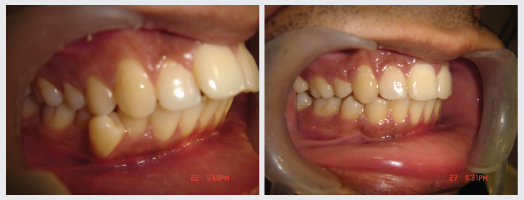

Orthodontics, popularly known as Braces treatment is a speciality of Dentistry that deals with the correction of Malocclusion or Malalignment. It is used to correct crowded teeth, protruded teeth, dental spaces, Jaw Deformities, improper bites and crooked smiles. At DENTAL QUE Orthodontic treatment is done for all age groups and there are types of braces available to suit everyones needs.